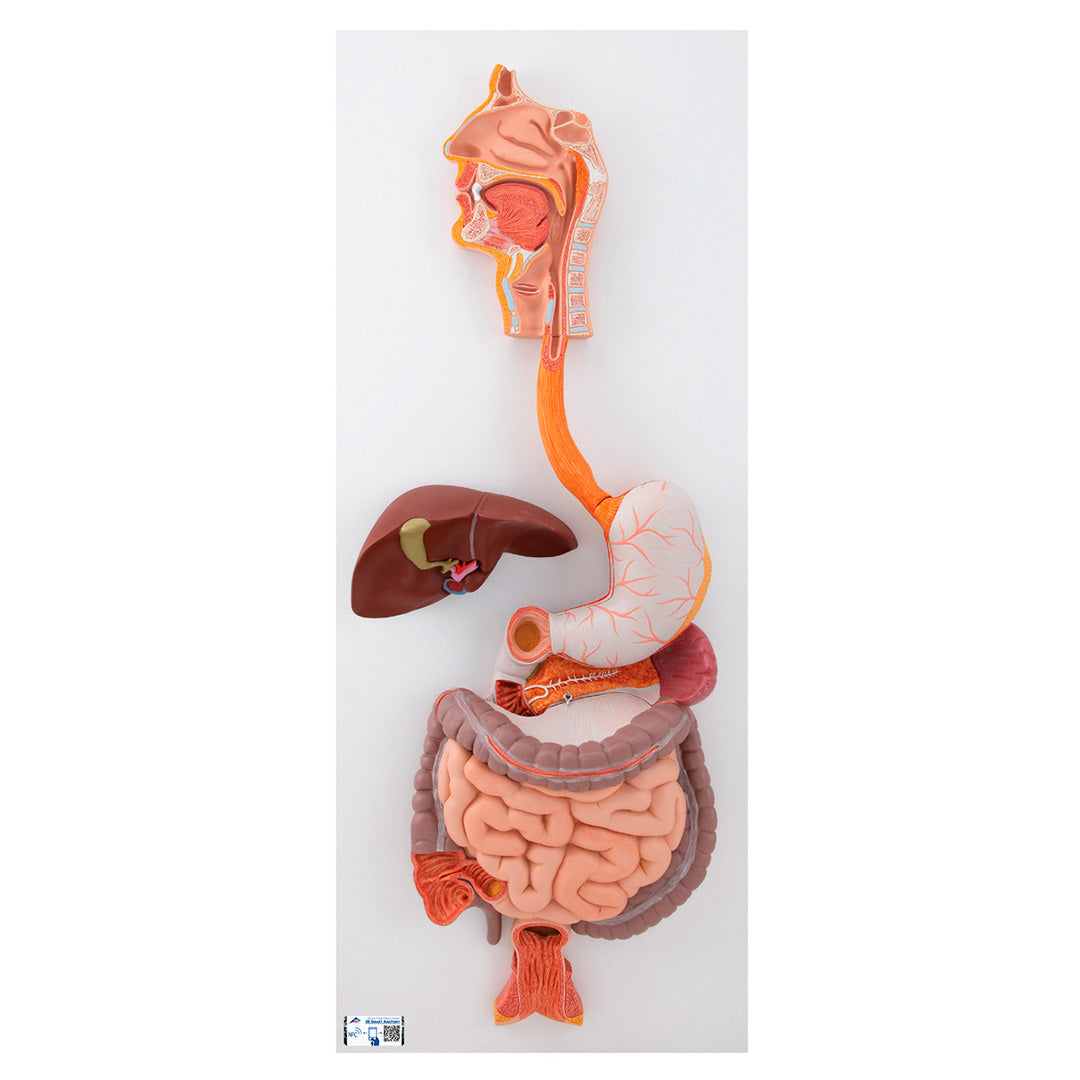

El sistema digestivo, de 3 piezas

El sistema digestivo, de 3 piezas

Modelo en tamaño natural que muestra todo el sistema digestivo en relieve gráfico.

Características:

• Nariz

• Cavidad bucal y faringe

• Esófago

• Tracto gastro-intestinal

• Hígado con vesícula biliar

• Páncreas

• Bazo

El duodeno, el ciego y el recto están abiertos.

El colón transversal y la pared delantera del estómago se pueden desmontar.

Sobre tablero.

Dimensión: 81 x 33 x 10 cm